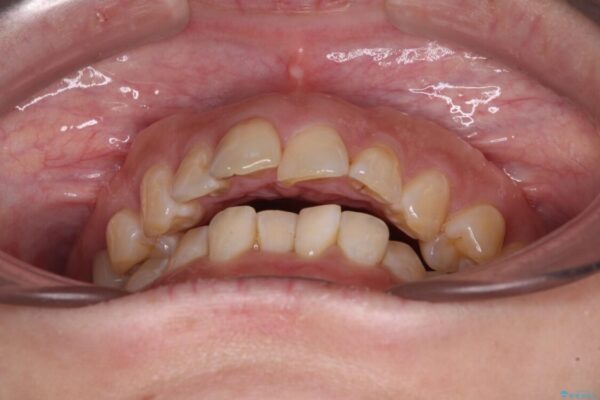

治療前

飛び出た上の前歯を気にして来院された患者様です。

奥歯の咬み合わせは、上顎歯列が理想的な一よりも数mm前方にある状態でした。